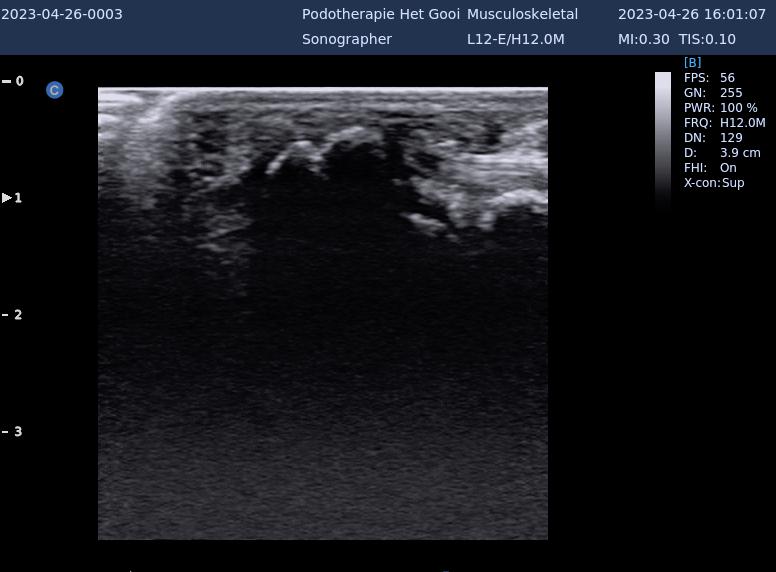

Sesamoïditis

Ontsteking van de pezen in de omgeving van de sesambeentjes bij het grote teengewricht

bipartite sesamsbeentje